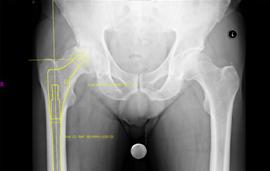

Hip and Pelvis Radiographic Positioning with Markers

When a radiologic technologist takes a radiograph of the hip for joint replacement, the image should include the upper third of the femoral shaft. When using a sphere with an arm and suction cup or stand, you will first need to adjust the arm so that the ball is the same distance from the image receptor as the greater trochanter.

When placing a scaling marker for hip x-rays, the greater trochanter provides a good palpable bone landmark in the plane of the hip joint. Positioning the marker on the skin over the greater trochanter should work well if this can be accommodated. However, often orthopedists like to have a whole pelvic view for templating hips so that leg length inequality can be recognized and also because it is often helpful to template the comparison side. If a pelvic view is taken, a 14 x 17 field is often barely large enough to include the bones and often miss the soft tissues overlying the greater trochanters. So in some cases, the marker will need to be positioned between the thighs. To do this, first, position the sphere at the level of the greater trochanter on the lateral side of the pelvis, equivalent to the hip joint level. This is to adjust the arm so that the sphere is the correct height. Then, move the marker carefully without changing the shape of the arm, to the same vertical height level between the thighs where it will be visible in the radiation field.